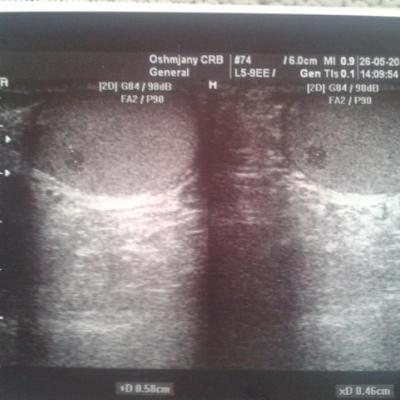

Сегодня на узи врач поставил такое заключение: "правое яичко до 45x24x32 мм., Левое - до 46х24х21 мм. В правом яичке узловое образование смешанной эхогенности до 5.8Х4.6Х4.5 Мм. С довольно четким контуром, однородное. Придатки без особенностей. Свободная жидкость в мошонке не визуализируется. Заболевание правого яичка?"